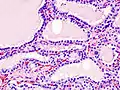

The most common presenting symptoms are: rapid weight loss, tachycardia (rapid heart rate), vomiting, diarrhea, increased consumption of fluids (polydipsia), increased appetite (polyphagia), and increased urine production (polyuria). Other symptoms include hyperactivity, possible aggression, an unkempt appearance, and large, thick claws. Heart murmurs and a gallop rhythm can develop due to secondary hypertrophic cardiomyopathy. About 70% of affected cats also have enlarged thyroid glands (goiter). 10% of cats exhibit "apathetic hyperthyroidism", which is characterized by anorexia and lethargy.[62]